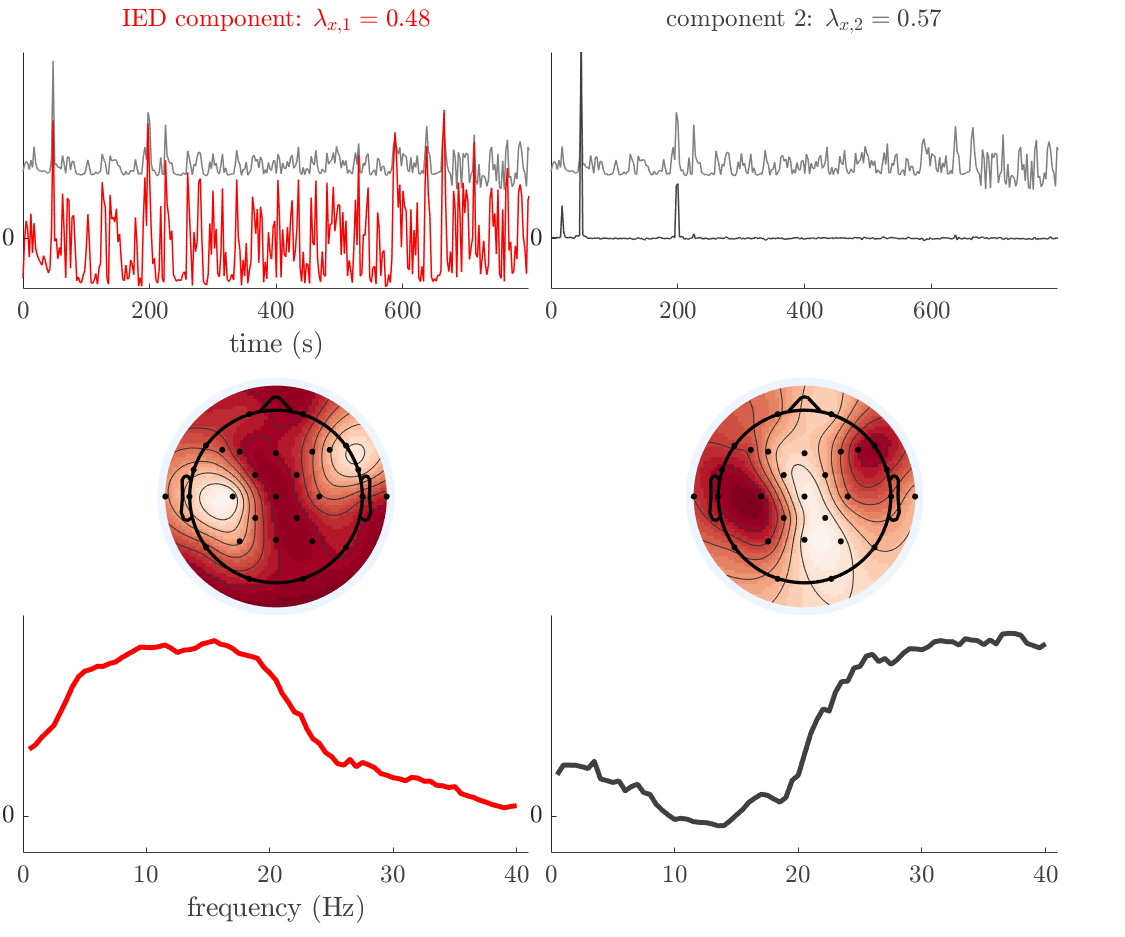

We analyze the solution with sources. Figure 1 shows the EEG signatures and HRF waveforms. One of the sources is highly correlated to the MWF reference (in grey), which was already known from Table B.3. This IED-related source had a typical low-frequency spectrum, which is expected for the typical spike-and-wave interictal discharges. The topography is relatively diffuse, although the highest amplitudes are mostly in the left hemisphere. This is in accordance with the lateralization of ictal onset zone (left temporal lobe, cfr. Table 1). There are some noteworthy observations to be made about some of the other components. The fourth has an unusually sharp spectrum, is mainly localized on two nonadjacent center electrodes, and is sustained for a single period of many seconds Hence, this component likely captured an artifact (of yet unknown origin), although we spotted no large-amplitude changes in the EEG itself. Similarly, the third source is only present at one frontal electrode, and exists in a frequency range above 20 Hz. It might represent a muscle artifact, e.g., due to frowning or twitching of some muscles in the forehead. The HRFs of all ROIs are shown in Figure 1(b). Two of the basis functions seem to have converged to a very similar waveform, which is an unfortunate possibility if two initial HRFs are too close to the same local optimum in their respective parameters. This reduces the expressive power of the basis set, which is clearly visible, since many ROIs have a nearly identical HRF. One of the twenty ROIs with the highest-entropy HRF overlapped the IOZ, although clearly this HRF (bold line) is not among the most dissimilar waveforms for this patient. This is also visible in Figure 2: both the HRF entropy and extremity maps show a small overlap with the delineated IOZ. Despite the good correspondence in the EEG domain, no significant (de)activation of the IED-component is found inside the IOZ.

We analyze the solution with sources, and show the results in Figure 3 and 4. As for patient 1, we found a source which is strongly correlated to the MWF envelope, and which had a mostly low-frequency behavior characteristic for spikes. The topography is mostly uninformative, and does not clearly correspond to the patient’s clinical data. The third source is mostly present at both sides of the head, is very sparsely active in time, and has a high-frequency content: this is most likely an artifact due to the neck muscles. Again, there is one of the highest-entropy HRFs which belongs to a ROI in the IOZ. Now, the waveform is clearly resolved from the other HRFs, through the strong initial dip (before 0 seconds). Such a dip is sometimes observed in HRFs, but its underlying physiological mechanism is not yet fully understood. It is possible that this dip reflects altered vascular autoregulation near the IOZ (cfr. the explanation in the Section 1 of the main text), or a rapid depletion in oxygen due to IED generation (before the IED becomes visible on the EEG). Figure 4 furthermore shows that the IED-related component is significantly active in parts of the IOZ, and deactive in others. As mentioned earlier, this deactivation may or may not be due to errors in sign correction. Interestingly, the ROI with the high alteration in neurovascular coupling is distinct from both the activated and deactivated ROIs.

We analyzed the solution with sources, and show the results in Figure 5 and 6. There is one source which is mostly correlated to the reference (but not extremely, see also Table B.3). This source had a right-temporal focus, conform the diagnosis in Table 1. The second source illustrates the phenomenon of an erroneous sign exchange between the spatial and spectral profiles. Also one of the HRFs has a negative polarity, which is a failure of the sign correction procedure (in this case, because there is exceptionally no positive overshoot). However, the HRF variability metrics are still interpretable, and indeed two ROIs among the ones with the highest-entropy HRFs overlap with the IOZ. The IED component is significantly active in a tiny portion of the IOZ (cfr. Figure 6). The second source is significantly active in symmetrical parts of the parietal lobe. Given its ongoing fluctuation over time, we hypothesize that this source captures a resting state network (RSN).

We analyze the solution with sources, and show the results in Figure 7 and 8. There is a clear IED-related component, with a very high correlation to the MWF reference, a typical spectrum, and an anterior-temporal focus, which corresponds very well to the patient’s diagnosis (cfr. Table 1). The fifth source seems present at only one channel, and has spectral harmonic at Hz and Hz. One of these peaks is reminiscent of the fourth component in patient 1. As Figure 8 shows, the HRF entropy and extremity prove to be strong biomarkers for the IOZ in this case, and also the significant IED activation and deactivation allow correct localization. In Figure 7, it is clear that some HRFs may still have the wrong sign, which means that the interpretation of ‘active’ and ‘deactivated’ is flipped in those ROIs. Hence, regions of significant deactivation are in fact significantly activated. The fourth source had a significant overlap with the auditory RSN, and its spectrum reveals activity in the band.

We analyze the solution with sources, and show the results in Figure 9 and 10. One source is strongly correlated to the MWF, while the other source is likely an artifact, given its very sparse temporal profile. Both sources coincide at one high-amplitude peak, by which we infer that this is probably an artifactual period in the signal. Indeed, when inspecting the original EEG signals, we found high-frequency muscle artifacts at these times. This source also had no significant activation in its spatial map, which corroborates its non-neuronal origin. The IED-related source had a broader spectrum than most other cases, and an uninformative topography. None of the ROIs with high-entropy HRFs is located in the IOZ. The pseudo t-map provides correct localization of the IOZ, however.

We analyze the solution with sources, and show the results in Figure 11 and 12. We found a clear IED-related component, with a characteristic spectrum and a topography which is backed up by the patient’s diagnosis (left anterior-temporal IOZ). The fourth source has a very similar topography and spectrum to the fifth source in patient 5. One HRF inside the IOZ had a high-entropy, and is distinguishable from the others by its very sluggish waveform, i.e., it is smeared out in time, with no sharp over- or undershoot. Also the pseudo t-map provided an accurate localization of the IOZ. Notably, in this patient, the extremity metric misses the deviating HRF in the IOZ (while the entropy metric picks it up). The second source overlapped with the frontal part of the default mode network (DMN), and is active in the and low bands.

We analyze the solution with sources, and show the results in Figure 13 and 14. We found two components which had correlated time courses. At the time of the peaks, we found higher-amplitude events in the EEG with dubious origin, hence they may or may not be artifacts. One of both components is more strongly correlated to the MWF, and its activation is concordant with the IOZ. The second component shows high overlap with the sensorimotor network. For this patient, none of the IOZ’s ROIs had extreme values of either HRF metric.

We analyze the solution with sources, and show the results in Figure 15 and 16. In this patient, there is only a moderate correlation of a component with the MWF reference time course. This component’s topography (left occipital) agrees with the clinical description, however. The HRF extremity (and not the entropy) is high in a small part of the IOZ. Both the significant IED activation and deactivation allow correct localization as well. The second source seemingly captured high-frequency oscillatory activity in the sensorimotor network, similar to the previous patient.

We analyze the solution with sources, and show the results in Figure 17 and 18. The IED-related source had a high correlation with the MWF reference, but an odd bimodal spectrum. Its EEG topography is very consistent with the clinical description. Both HRF extremity and entropy are useful biomarkers for the IOZ. The IED activation and deactivation maps each had a very small overlap with the IOZ. The second source is temporally sparse and captures high-frequency EEG variations, which we identified as muscle artifacts.

We analyze the solution with sources, and show the results in Figure 19 and 20. Again we observe an IED-related source and a seemingly artifactual source with a spectral peak near 34 Hz. Many of the high-entropy HRFs are highly noncausal, and are associated to ROIs inside the IOZ. Hence, with both HRF metrics, the highest-scoring ROIs provides good localization of the HRF. While there are no significantly active ROIs in the IOZ, there are several significantly deactivated ROIs, which may indicate that the sign standardization was not done flawlessly (cfr. also some of the negative-peaking HRFs for patient 10). Surprisingly, the second source had one significantly active ROI, which overlaps with the IOZ, but which did not match its EEG topography. Hence, the nature of this source remains ambiguous.